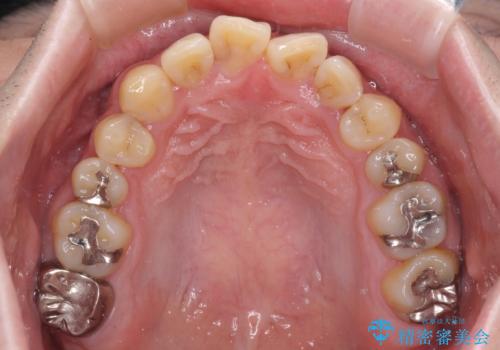

- デコボコした前歯をセラミックできれいに揃えたいとのことで来院された患者様です。

歯を削って整えることは簡単ですが、健全な歯を削って後悔してからでは遅いため、矯正治療を提案しました。

はじめは矯正治療の期間が長いことに悩んでいらっしゃいましたが、ある程度整えば満足するだろうとのことで、インビザラインにて矯正治療を行うこととしました。

左上の犬歯が欠損しているため、正中の位置や奥歯の咬み合わせが理想的にならない点を了承していただきました。